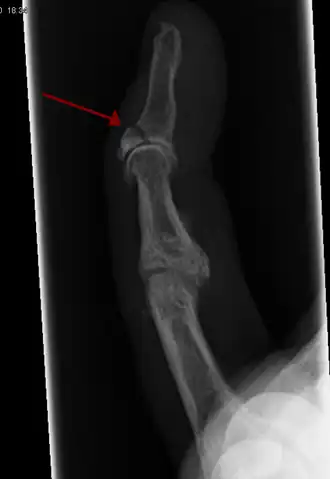

La radiografía que muestra fractura en la inserción del tendón extensor

-